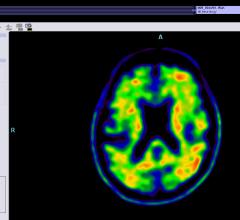

April 26, 2016 — Repeated head impacts to high school football players cause measurable changes in their brains, even ...